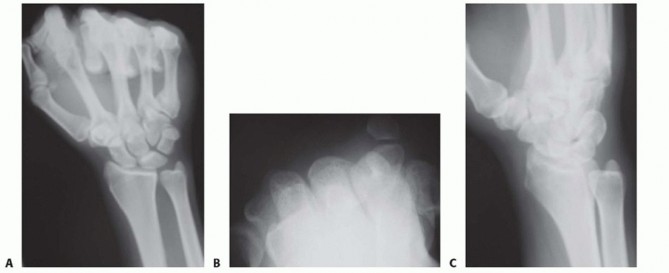

Imaging serves as our architectural blueprint for surgical planning. We mandate a comprehensive plain radiographic series. This begins with strictly neutral rotation posteroanterior (PA) and lateral views of both wrists to accurately assess static ulnar variance and the morphology of the sigmoid notch. However, static views are insufficient. We must obtain a pronated grip view (the clenched fist PA). As Tomaino and others have definitively demonstrated, active power grip forces the radius proximally relative to the ulna, increasing dynamic ulnar variance by an average of 2.5 mm. This view often unmasks profound dynamic impaction in wrists that appear neutrally variant on resting films.

Clinical & Radiographic Imaging Archive